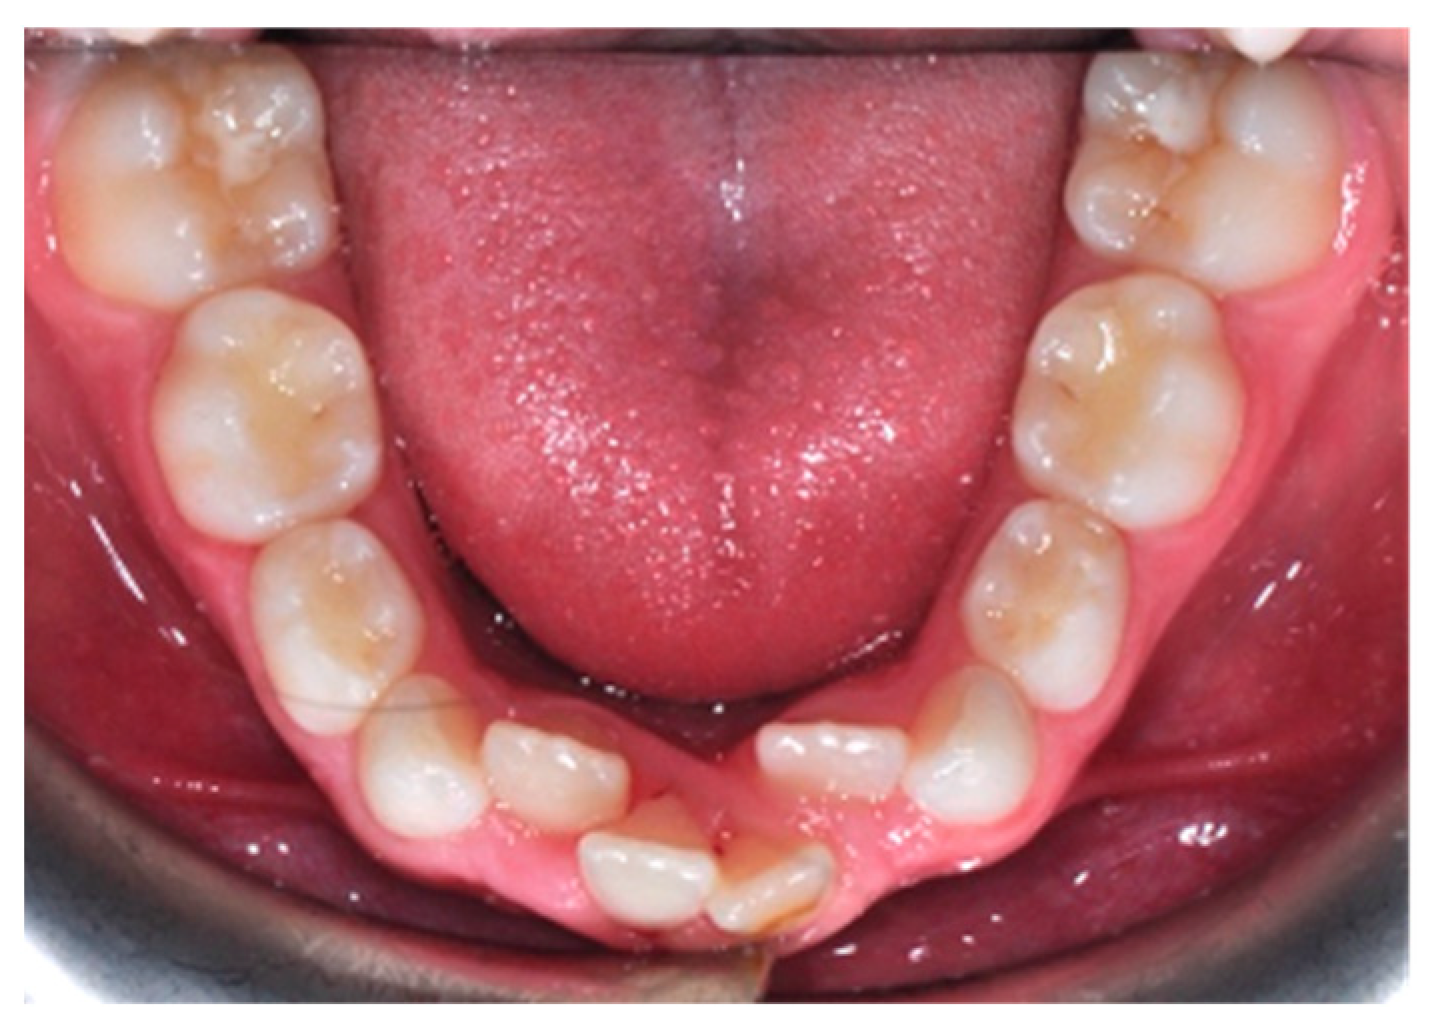

Crowding is a common orthodontic malocclusion with a strong hereditary tendency. It is caused by a variety of factors, including the impact of environmental and genetic factors on dental arch dimensions [1]. Dental crowding is defined as an inconsistency between tooth size and arch dimension that results in malocclusion; it occurs because of a lack of coordination between tooth size and arch dimensions [2,3,4,5]. The lower incisors are the teeth most frequently involved [6,7,8] (Figure 1).

Figure 1. Crowding of the permanent mandibular incisors.